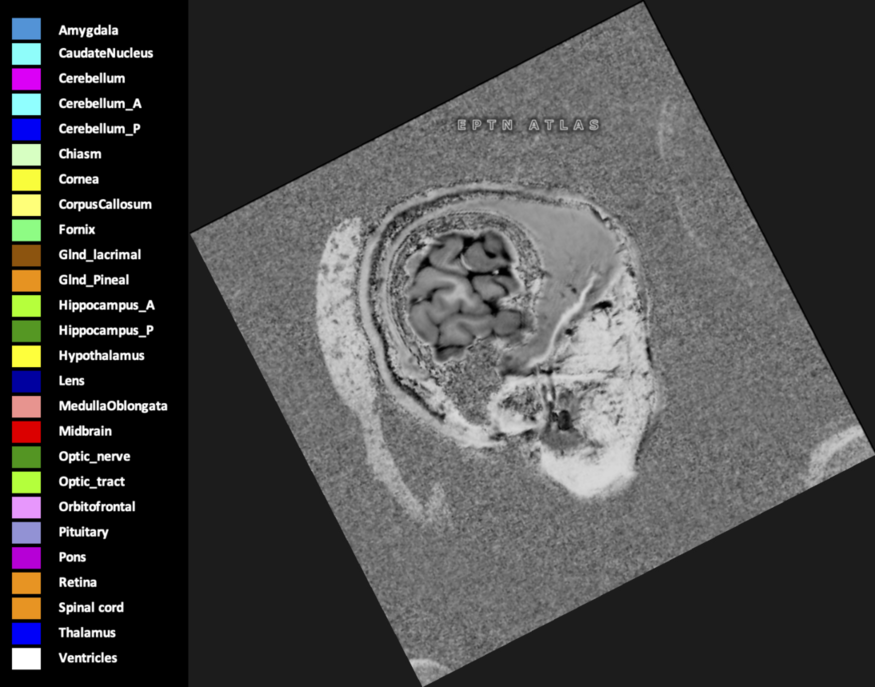

Three-dimensional delineation of the 25 consensus OARs for neuro-oncology are shown on CT (WW/WL 120/40, 3000/600), 3T MR images, (T1Gd, T2FLAIR 1mm) and 7T MR (MP2RAGE 0.7 mm). All are presented in transversal, sagittal and coronal view.